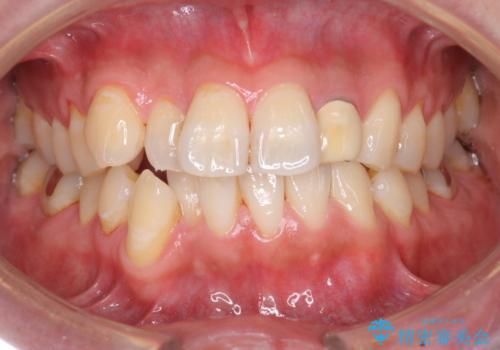

- 結婚式を控えており、それまでに歯を白くしたいということで来院されました。

歯医者に来院するのが久しぶりの様で歯の表面に汚れが付着しているとホワイトニング薬剤の効果が薄れるため、術前のクリーニングをおすすめしその後オフィスホワイトニングエクセレントコースを行いました。

全体的にトーンアップしました。オフィスホワイトニングはホームホワイトニングに比べ1度で白くなりやすいため、直近の予定を控えている方にお勧めしております。